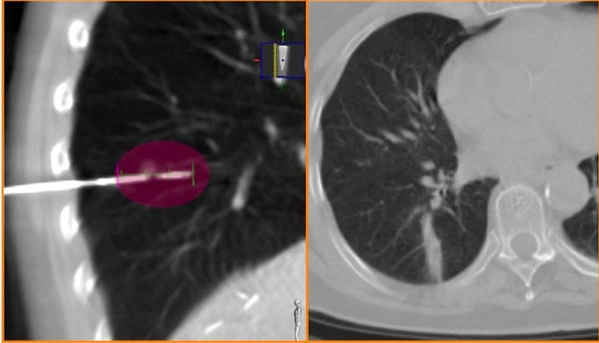

Il riconoscimento del tipo di tumore polmonare è ciò che si definisce diagnosi. Identificare il tipo di tumore è fondamentale per guidare il medico nella scelta delle opzioni terapeutiche più adatte e mirate. Solo in rarissimi casi, come nel caso di altre patologie concomitanti o di condizioni generali del paziente che non permettono un approfondimento diagnostico completo, si può evitare di procedere all’identificazione specifica del tipo di tumore.

In ogni caso, l’identificazione del tipo di tumore polmonare è cruciale, poiché consente di personalizzare il piano terapeutico e migliorare la risposta al trattamento, aumentando le possibilità di guarigione o di controllo della malattia. La diagnosi accurata è il primo passo per determinare la strategia terapeutica, che può includere opzioni come chirurgia, radioterapia, chemioterapia, e trattamenti più recenti come la terapia mirata e l’immunoterapia, a seconda del tipo di carcinoma polmonare identificato.